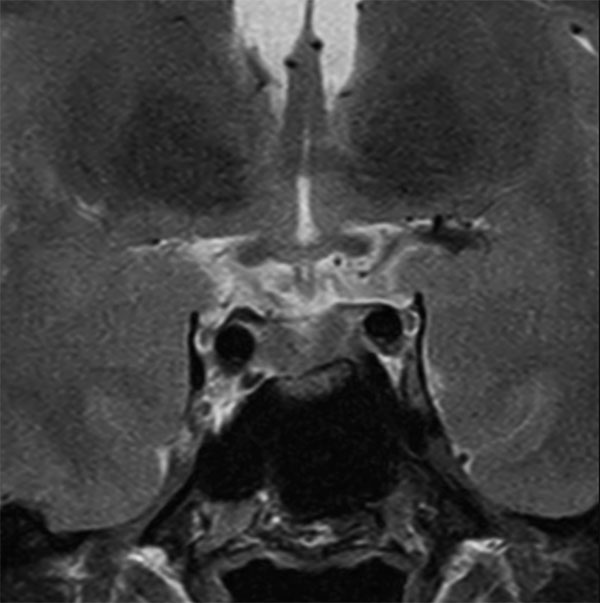

Subtle 4mm focus of decreased enhancement in the right pituitary posteriorly. No definite discrete lesion is demonstrated and the findings are equivocal for a microadenoma. Follow up imaging with MRI in six months is indicated. No suprasellar lesion or no other intracranial abnormality is demonstrated.

Coronal T2w TSE